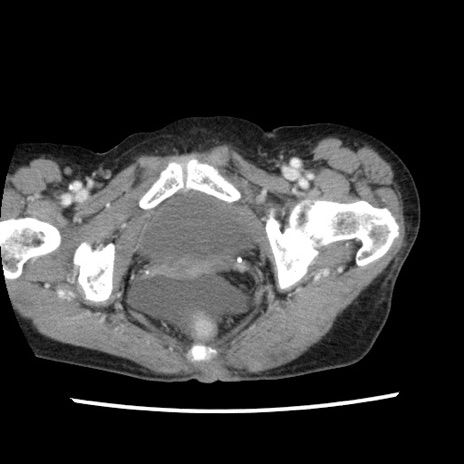

症例1(横断像)

【症例】80歳代女性

【主訴】腹痛

【現病歴】8時間前から腹痛あり来院。

【既往歴】糖尿病、脂質異常症、子宮体癌にて子宮全摘術

【身体所見】意識清明・会話良好だが腹痛で苦悶様、全腹部にわたって反跳痛と圧痛あり

【データ】WBC 13600、CRP 0.14、LDH 224、CK 90